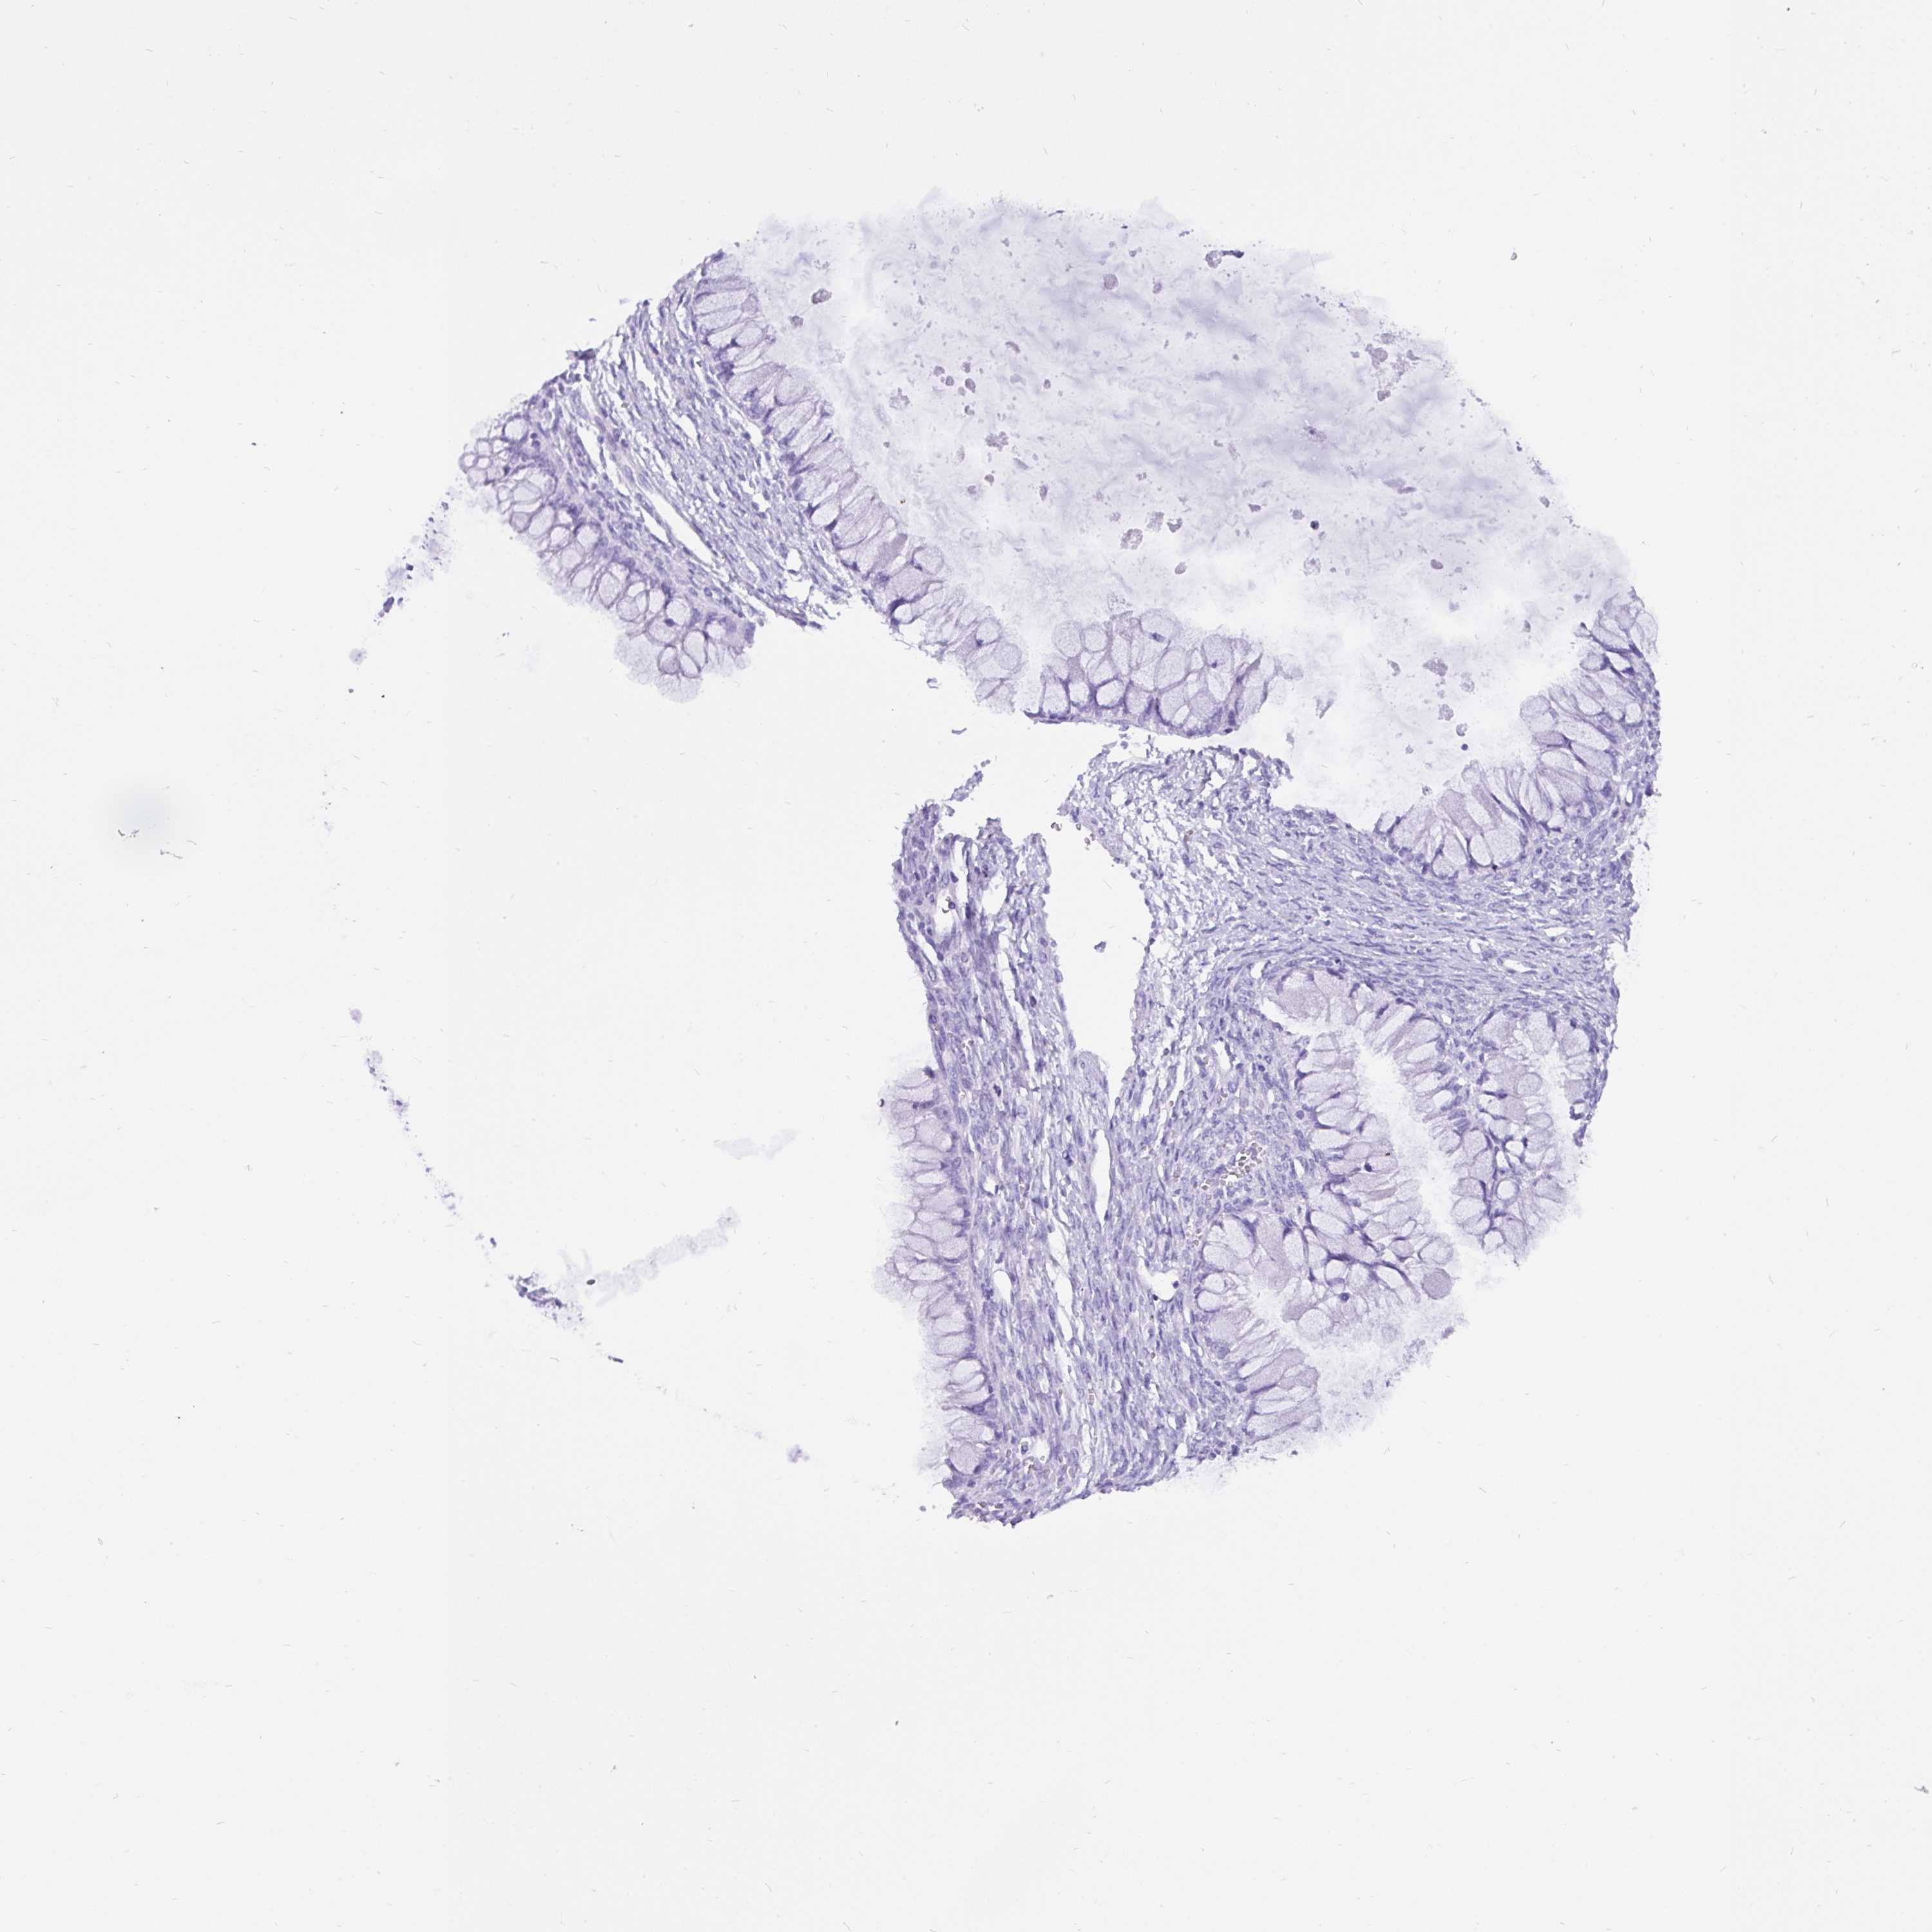

OVARIAN CANCER - Protein expressioni

A mouse-over function shows sample information and annotation data. Click on an image to view it in a full screen mode. Samples can be filtered based on level of antibody staining by selecting one or several of the following categories: high, medium, low and not detected. The assay and annotation is described here.

Note that samples used for immunohistochemistry by the Human Protein Atlas do not correspond to samples in the TCGA dataset.

Antibody stainingi

Antibody staining in the annotated cell types in the current human tissue is reported as not detected, low, medium, or high, based on conventional immunohistochemistry profiling in selected tissues. This score is based on the combination of the staining intensity and fraction of stained cells.

Each image is clickable and will lead to virtual microscopy that enables deeper exploration of all samples and also displays staining intensity scores, fraction scores and subcellular localization as well as patient and tissue information for each sample.

Antibody HPA030877

Antibody CAB000133

Staining

High

Medium

Low

Not detected

Intensity

Strong

Moderate

Weak

Negative

Quantity

>75%

75%-25%

<25%

None

Location

Nuclear

Cytoplasmic/membranous

Cytoplasmic/membranous,nuclear

Cystadenocarcinoma, serous, NOS

Carcinoma, NOS

Cystadenocarcinoma, mucinous, NOS

Carcinoma, endometroid